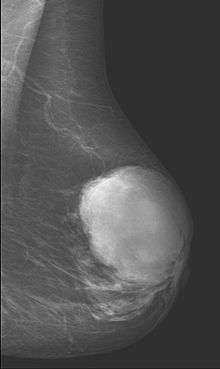

This is predominantly a tumor of adult women, with very few examples reported in adolescents. Patients typically present with a firm, palpable mass. These tumors are very fast-growing, and can increase in size in just a few weeks. Occurrence is most common between the ages of 40 and 50, prior to menopause. This is about 15 years older than the typical age of patients with fibroadenoma, a condition with which phyllodes tumors may be confused. They have been documented to occur at any age above 12 years (reference needed).